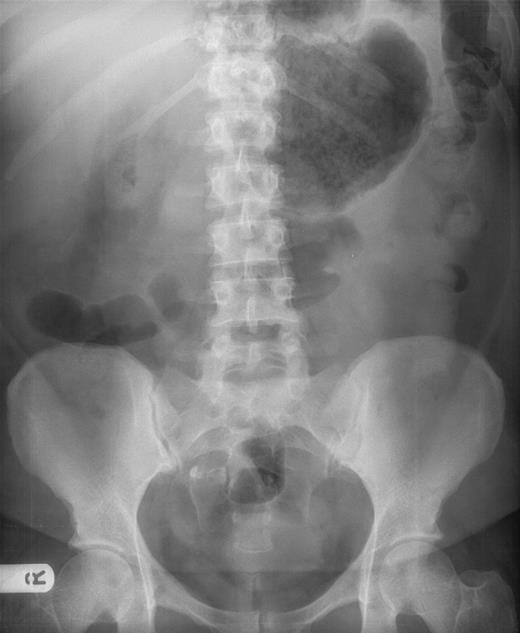

Plain abdominal radiography (Fig. 1) displayed a dilated viscus in the left upper quadrant with absence of colonic shadow on the right side of the abdomen. Initially this was reported as a large distended stomach, but in retrospect was thought to be the caecum.

Abdominal X-ray showing dilated viscus in the right upper quadrant, initially reported as large distended stomach, in retrospect thought to be the caecum.